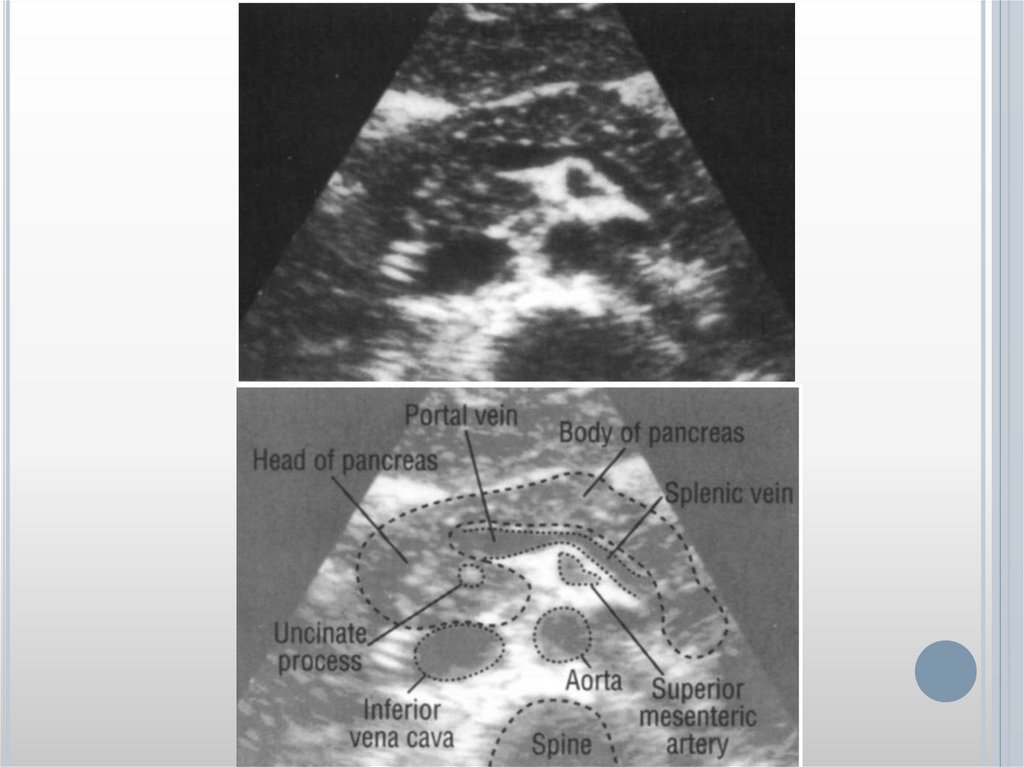

ОСТРЫЙ ПАНКРЕАТИТ